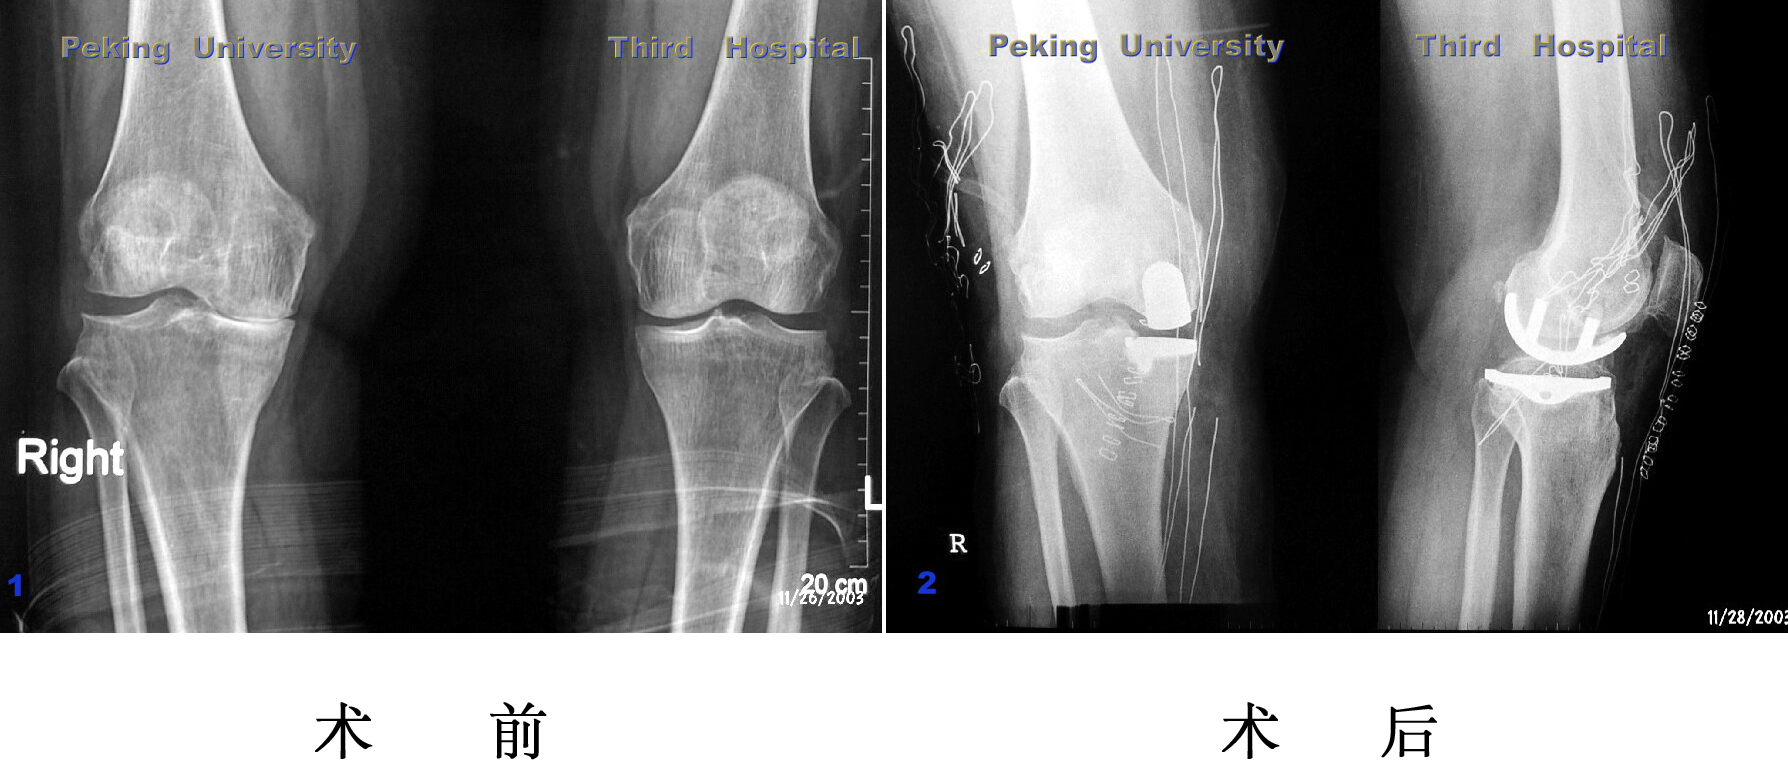

胫骨截骨

胫骨植骨

严重膝内翻,胫骨平台内侧植骨,软组织松解,术后内翻纠正